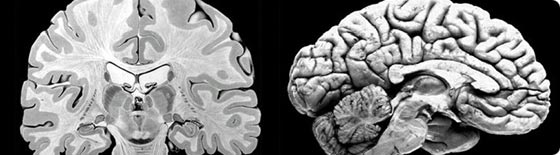

Historically, neural scientists have taken one of two somewhat parallel approaches to the complex problem of understanding the biological mechanisms that account for mental activity. The first, or molecular model, analyzes the nervous system in terms of its elementary components, by examining one molecule, cell, or circuit at a time. The second, or cognitive model, focuses on mental functions in human beings and animals in an attempt to relate behavior to higher-order features of large systems of neurons.

The course of the program, according to Rubinstein, was to "turn from reductionist to holistic approaches," looking first at what is known about cells and neural networks before addressing research into perceptions and behaviors. Participating scholars discussed current understandings and answers to key questions: How do the actions of individual neurons shape the function of neural populations? What is the underlying logic of signaling in complex neural circuits? How do dynamic mechanisms modify the processing of this information? And ultimately, how does the activity of neural ensembles generate cognitive and emotional behavior?

They also confronted some of the enduring mysteries regarding the biology of mental functioning: How does signaling activity in different regions of the visual system permit us to perceive discrete objects in the visual world? How do we recognize a face? How do we become aware of that perception? How do we reconstruct that face at will, in our imagination, at a later time and in the absence of ongoing visual input? What are the biological underpinnings of our acts of will?